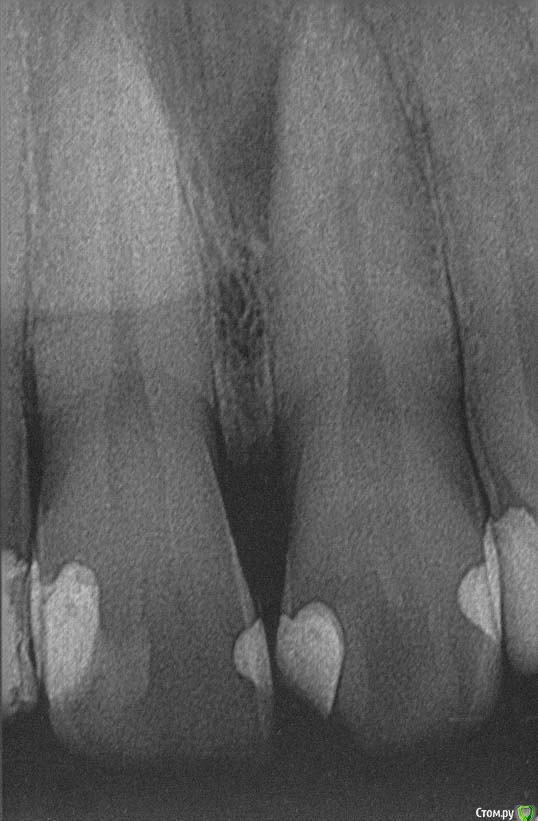

M@estro Опубликовано 9 июля, 2015 Автор Поделиться Опубликовано 9 июля, 2015 Тоже подниму тему. Травму отрицает, жалобы на потемнение. Витальность "-", перкуссия "-" , на рентгене подсказка - есть латераль. Вперёд, мыть ! 60 апекс, гибрид паковка. 1 час с пломбой 7 Ссылка на комментарий